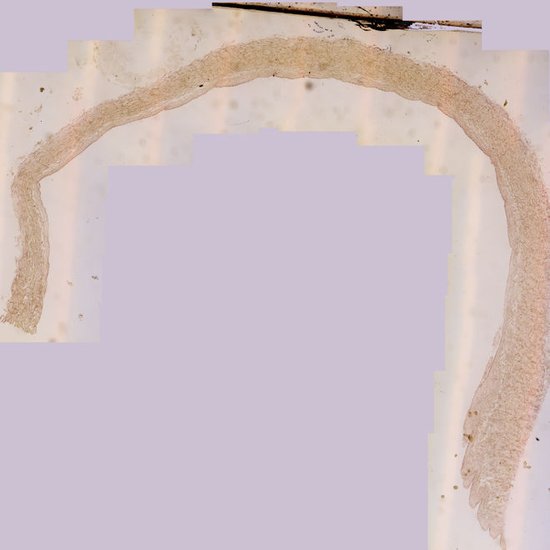

Large vein – cross-section through the vena cava showing elastic fibres (R/F)

Date: desember 2017 Author: marius loots Licence: Copyrighted